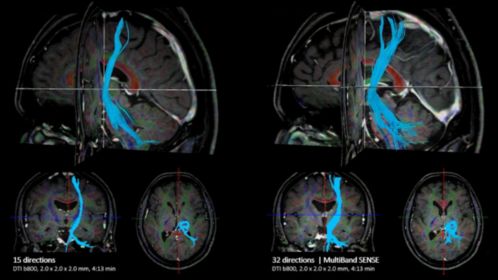

Excel in neuroscience with high gradient amplitudes of 65 mT/m and high slew rates of 220 T/m/s simultaneously, on each cartesian axis. Achieve up to 20% more fMRI sequences, with the same spatial resolution¹. Or acquire 50% more DTI directions in the same scan time³, by adding MultiBand SENSE acceleration. Due to efficient heat management (Grms of 27mT/m), the system can operate with the high average gradient amplitudes, required for DTI and fMRI imaging, without slowing down or overheating. Easy data transfer supports enhanced analysis outside of the default reviewing stations.